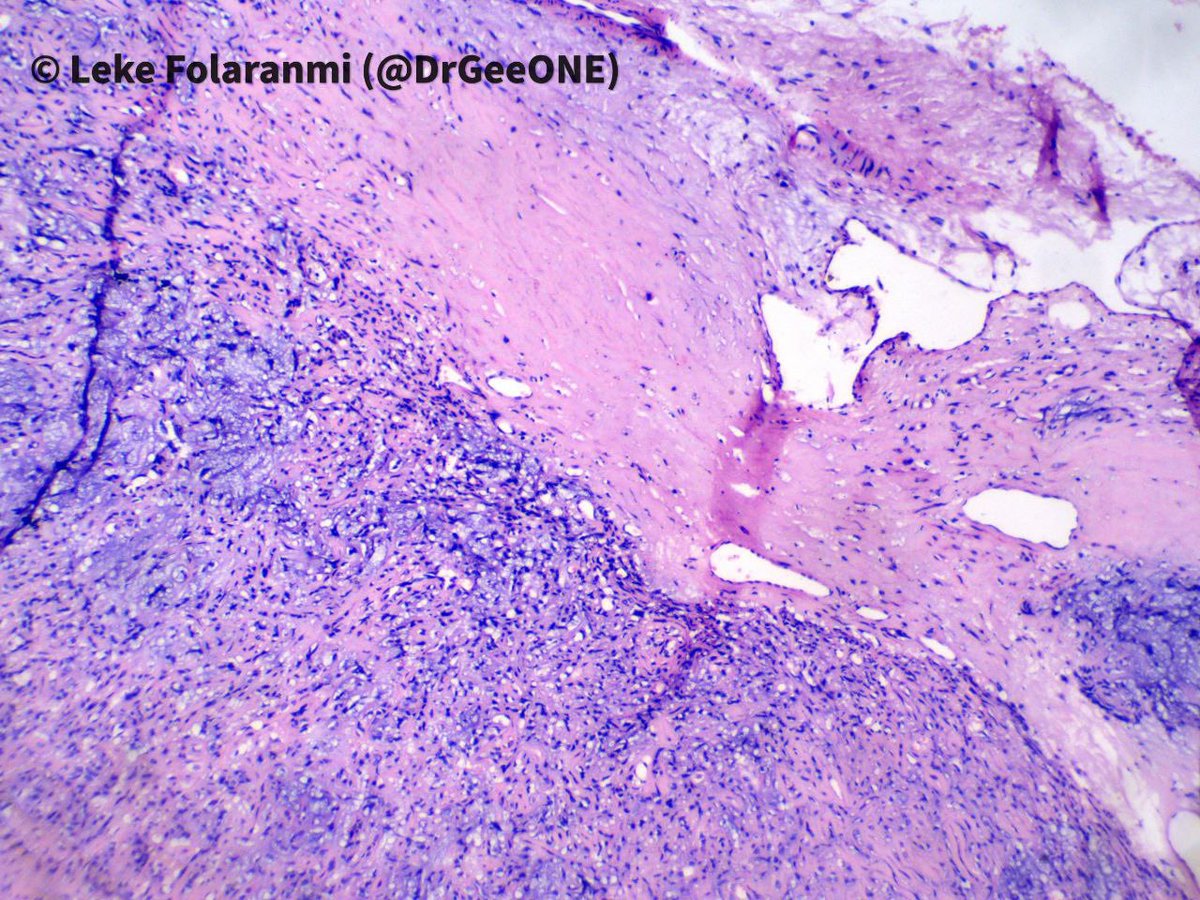

70s M h/o prostate cancer. Multiple bone lesions, this one from iliac. Dx/workup? #PathX #PathTwitter